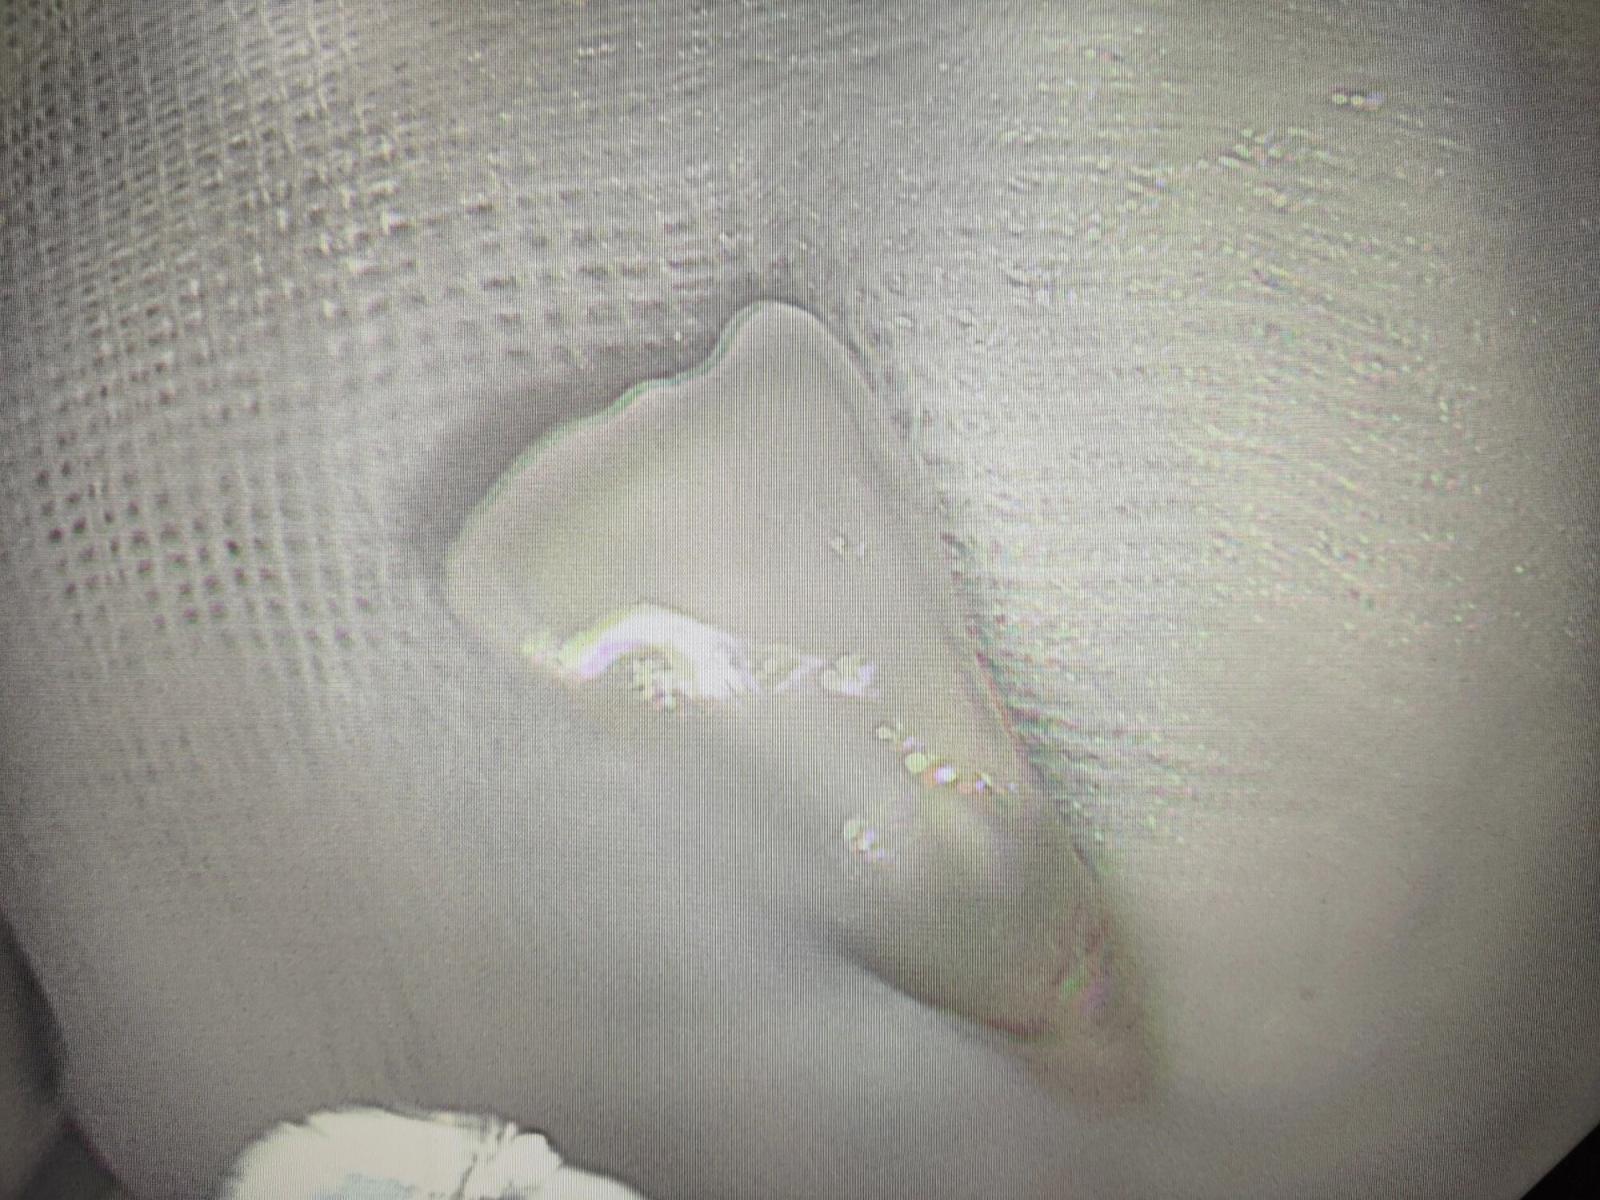

经过耐心探查,终于在气道入口处发现了那枚脱落的牙齿——它正随着老人的呼吸上下滑动,稍有不慎就可能坠入气道,后果不堪设想。考虑到牙齿位置特殊,若用异物钳直接夹取,极易因滑脱引发窒息,医护团队果断更换网篮器械,调整角度、精准瞄准,在反复尝试后,终于稳稳将牙齿套住并取出。